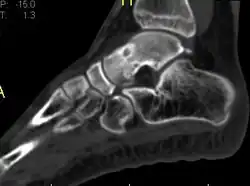

Radiographs in osteoid osteoma typically show a round lucency, containing a dense sclerotic central nidus (the characteristic lesion in this kind of tumor) surrounded by sclerotic bone. The nidus is seldom larger than 1.5 cm.

The lesion can in most cases be detected on CT scan, bone scans and angiograms. Plain radiographs are not always diagnostic. MRI adds little to the CT findings which are useful for localisation. Radionuclide scanning shows intense uptake which is useful for localisation at surgery using a hand held detector, and for confirmation that the entire lesion has been removed.[8][9]

1 b. Osteoid osteoma (side view): clearly seen by high resolution CT with a small well-defined lucent nidus in the mid tibial shaft.

2. CT scan showing an osteoid osteoma of the fibula with a clearly visible nidus

Nidus demonstrated by high resolution CT